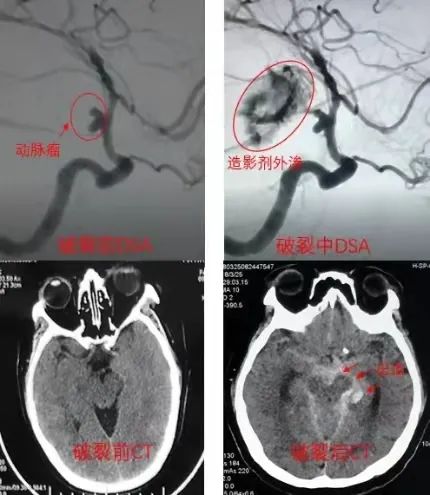

颅内动脉瘤的破裂